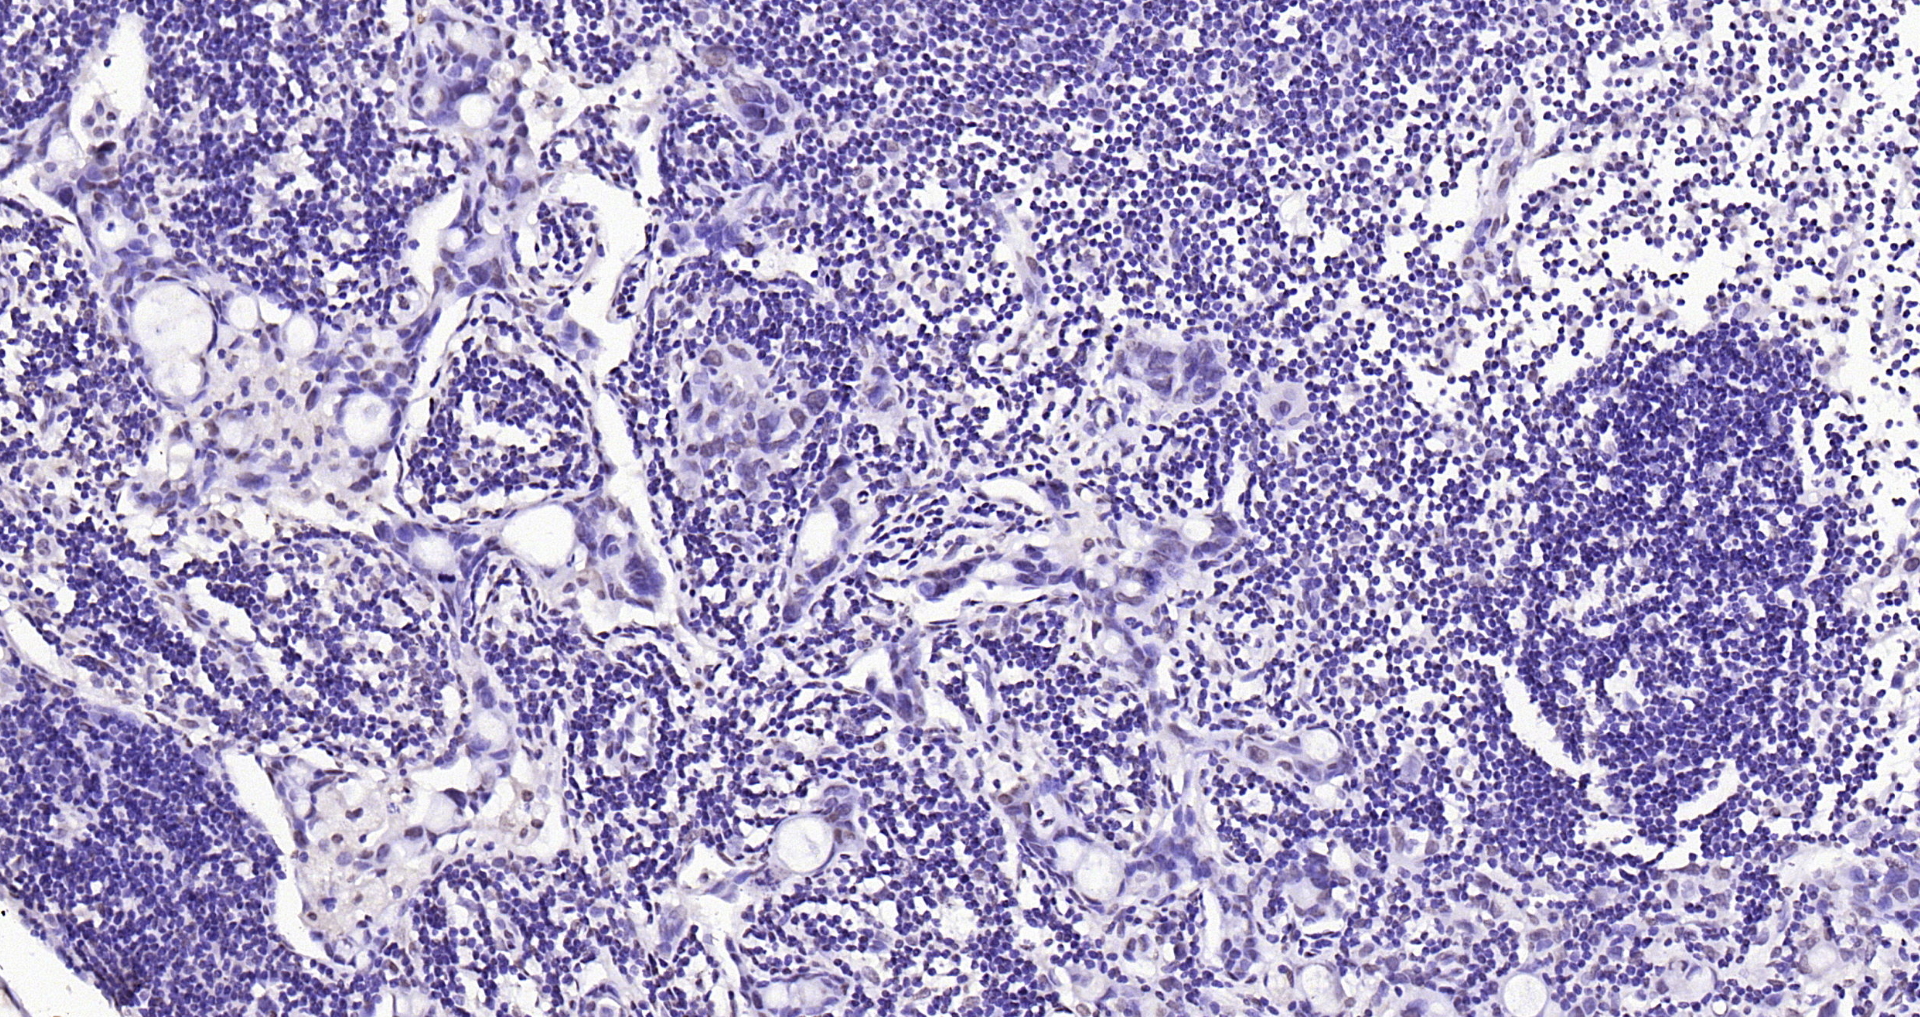

Paraformaldehyde-fixed, paraffin embedded Human colon cancer; Antigen retrieval by boiling in sodium citrate buffer (pH6.0) for 15min; Block endogenous peroxidase by 3% hydrogen peroxide for 20 minutes; Blocking buffer (normal goat serum) at 37°C for 30min; Antibody incubation with SOX9 Polyclonal Antibody, Unconjugated (bs-10725R) at 1:400 overnight at 4°C, DAB staining.

ApplicationsFlow Cytometry, ImmunoFluorescence, Western Blot, ELISA, ImmunoCytoChemistry, ImmunoHistoChemistry, ImmunoHistoChemistry Frozen, ImmunoHistoChemistry Paraffin

- Applications SupplierWB(1:300-5000), ELISA(1:500-1000), FCM(1:20-100), IHC-P(1:200-400), IHC-F(1:100-500), IF(IHC-P)(1:50-200), IF(IHC-F)(1:50-200), IF(ICC)(1:50-200)